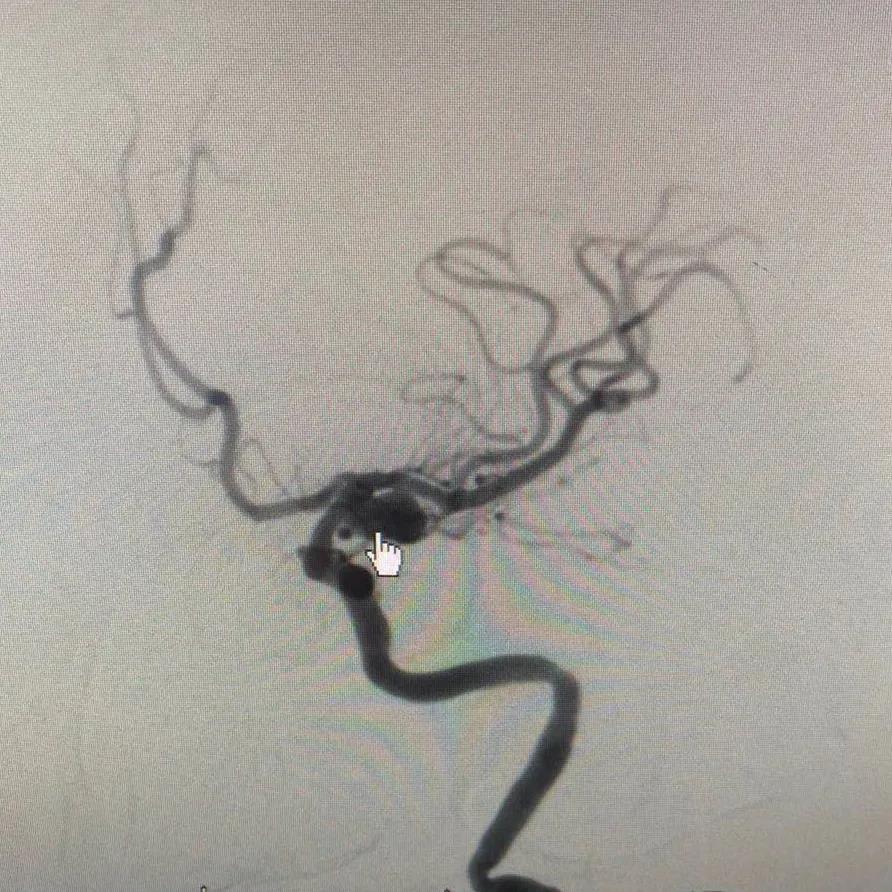

科主任郝琨检查后高度怀疑动脉瘤破裂出血,患者病情略平稳后立即急查头颈部CTA,确诊为“左侧后交通宽颈动脉瘤”,瘤颈宽约10mm,大小约3×7mm。由于该患动脉瘤瘤体大,传统方法动脉瘤夹闭或栓塞治疗难度都很高。

郝琨主任和魏庆生医生详细分析了患者病情,决定采用介入栓塞治疗。患者行DSA检查后发现主动脉弓扭转,导管进入困难,瘤体较CTA显示略大,最后决定给予患者行支架辅助弹簧圈栓塞术。支架辅助弹簧圈栓塞术本身难度就很高,加之患者瘤体大,给手术带来极大风险。郝琨主任凭借过硬的技术圆满完成手术,患者平安返回病房。